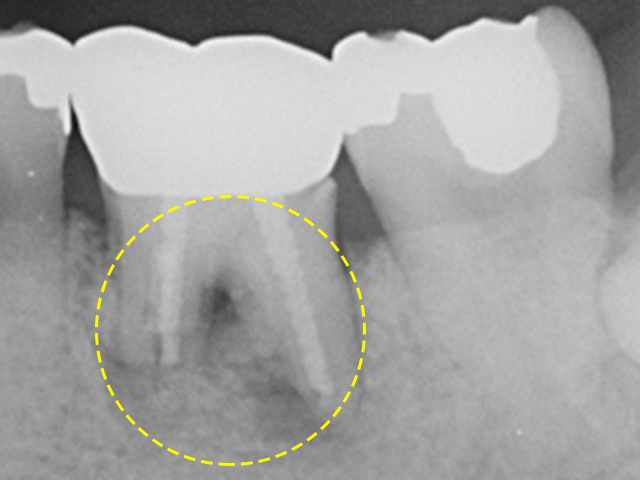

최창수치과에서는 최대한 본인 치아를 살릴 수 있도록 치주치료 및 골이식

등의 방법을 이용하여 주기적인 관리를 도와드리고 있습니다.

자연치아살리기를 실천하고 있는 최창수치과에서는 소중한 자연치를 살리고 보존하는 다양한 방법들을 보유하고 있습니다. 환자분들의 현재 구강 상태에 대해 세심하게 진료하여 파악함으로써 불필요한 발치가 진행되지 않도록 체계적인 시스템 아래 솔루션을 제공하고 있습니다.

자연치아 치료 과정